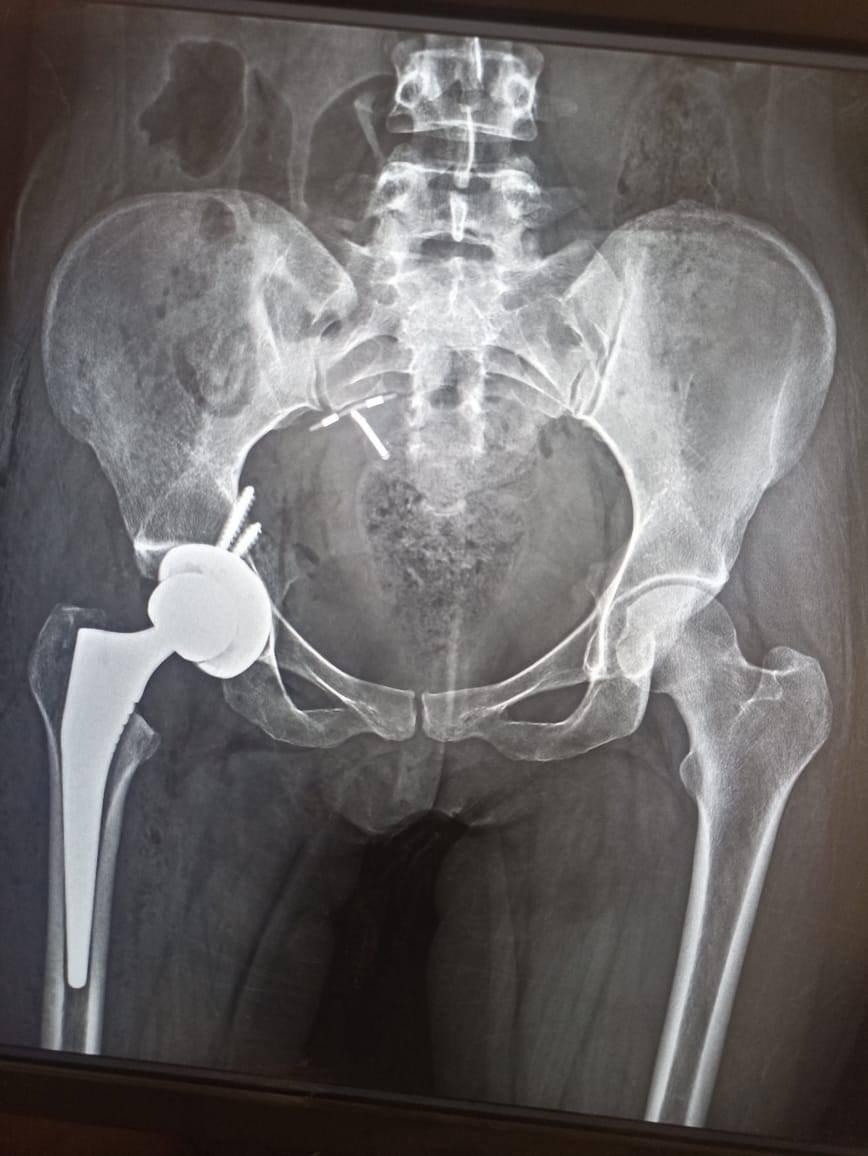

استمرارا للنجاحات الطبية التي تحققها مستشفيات جامعة أسيوط في مجال إجراء العمليات الجراحية الدقيقة نجح فريق طبي بوحدة المفاصل الصناعية بمستشفى الإصابات بجامعة أسيوط في إجراء جراحة تغيير كامل لمفصل الفخذ بمفصل كامل صناعي لا اسمنتي عن طريق التدخل المحدود الأمامي للفخذ لمريضة تعاني من تآكل بمفصل الفخذ، تحت رعاية الأستاذ الدكتور أحمد المنشاوي رئيس الجامعة، والأستاذ الدكتور علاء عطية عميد كلية الطب ورئيس مجلس إدارة المستشفيات الجامعية، والأستاذ الدكتور محمد الشرقاوي رئيس قسم جراحة العظام، وتحت إشراف الأستاذ الدكتور محمد عبد الحميد مدير المستشفى، والأستاذ الدكتور ياسر إمام خليفة رئيس وحدة المفاصل الصناعية.

كان فريق طبي بوحدة المفاصل الصناعية قد استقبل فتاة تبلغ من العمر ٣٤ عاما، وتعاني من تآكل بمفصل الفخذ، والمعتاد في هذه الحالات أن تتم عملية التغيير عن طريق التدخل الجانبي ويتم خلالها قطع جزء من العضلات إلا أن الفريق الطبي قام بإجراء عملية جراحية شديدة الدقة تجرى لأول مرة بصعيد مصر، للمريضة دون الحاجة إلى قطع للعضلات، وذلك من خلال فتحة صغيرة أمامية لا تتعدى ال ٥ سم، مما يتيح للمريضة العودة الوظيفية السريعة ويقلل من ضعف العضلات وحدوث العرج عقب الجراحة.